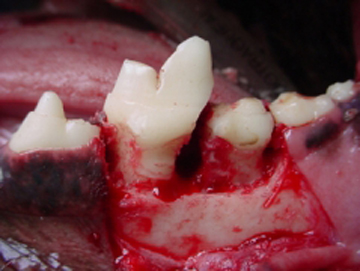

La cirugía en cavidad oral es una de las áreas más socorridas en odontología veterinaria. La extracción dental es el procedimiento que más se utiliza en México sobre todo en perros. La enfermedad periodontal es la causa más común de indicación para la extracción dental, siguiéndole las fracturas dentales por traumatismo y los problemas pulpares. La forma y disposición de las raíces en perros, gatos y otras especies carnívoras, hacen de la extracción un área muy difícil en casos de no existir enfermedad periodontal. En perros los problemas más comunes de extracción dental es de que las raíces de los dientes bi radiculares y tri radiculares están divergentes, por lo que siempre se tienen que seccionar quirúrgicamente las coronas hacia la furcación con el fin de separar las raíces para su extracción como si fueran dientes de una sola raíz aundo con el levantamiento de un colgajo mucoperióstico y ostectomía en la zona vestíbulo cervical. Los caninos es otro problema ya que el tercio medio de la raíz es más ancho que el tercio cervical, por lo que para su extracción se realiza la ostectomía de la cortical externa previo levantamiento de un colgajo mucoperióstico. La extracción de dientes en gatos presenta un problema básicamente y es que sus raíces son muy pequeñas y delgadas por lo que si no se tiene cuidado y paciencia regularmente se fracturan. La mayoría de casos que atendemos en nuestra práctica en gatos es la de restos radiculares por fracturas dentales iatrogénicas.

Haz CLICK sobre la imagen para ver descripción.Extracción del primer molar superior

Extracción de restos radiculares en un gato

Extracción de un canino superior